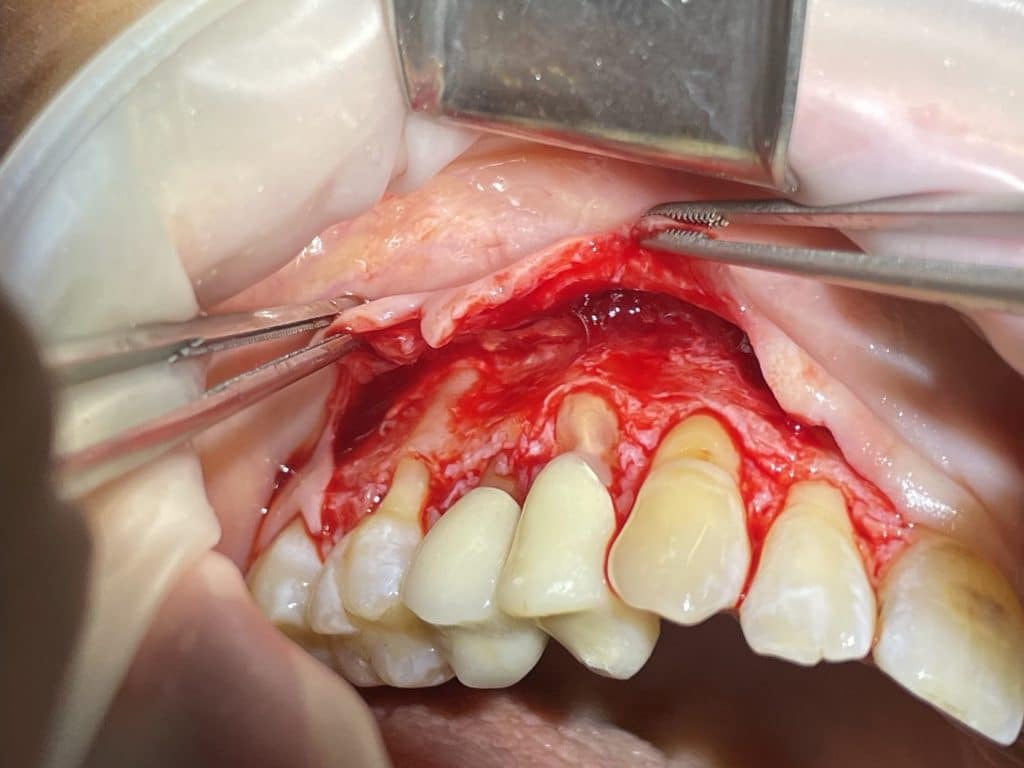

full and split thickness flap

connective tissue graft sutured

In quadrant 1, we initially removed caries and prepared tooth 14 for subsequent provisional cementation. We then performed a mucogingival surgery procedure, still utilizing the bilaminar technique with an envelope flap. The graft was harvested from the tuberosity area. The connective tissue was sutured to the periosteum, which had been left in place as the recipient bed. The primary flap was advanced coronally, covering the graft, and sutured with sling sutures in the most coronal position. In this case as well, the sutures were removed after 10 days.